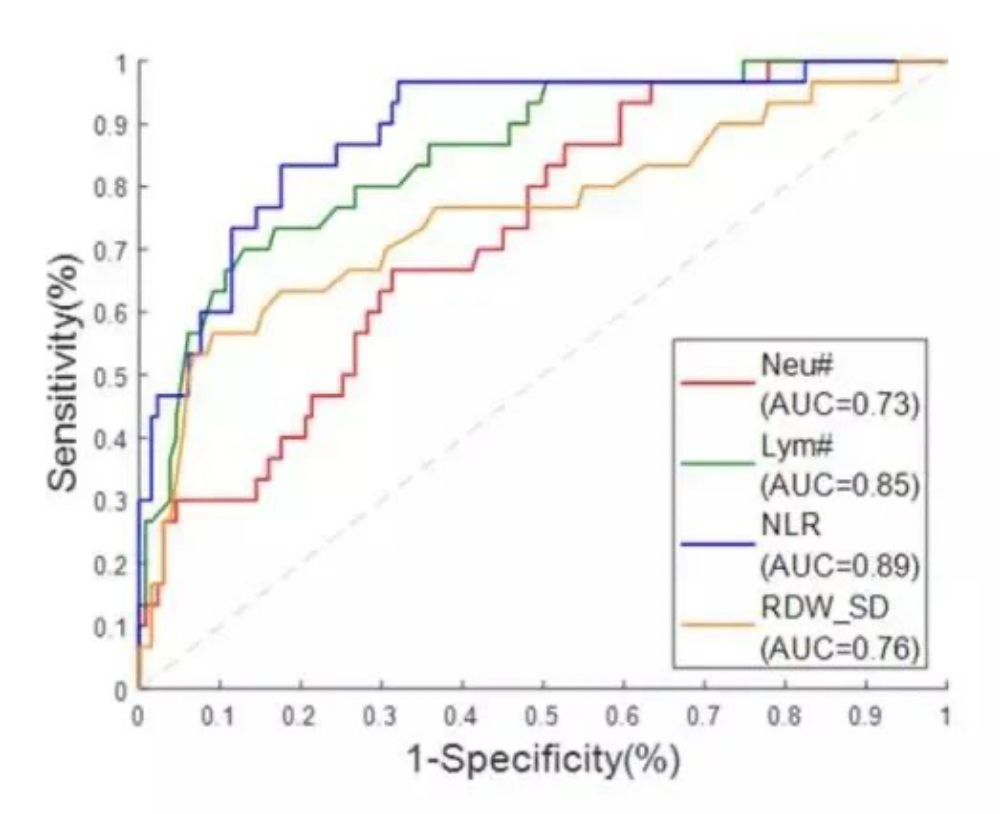

B. CBC parameters can help identify severe COVID-19 patients from moderate ones.

The first diagram below shows the receiver operating characteristic curve (ROC) of differentiating severe COVID-19 cases from moderate ones using hematology parameters. The positive samples demonstrated here are CBC results of severe cases, while the negative samples are those of moderate cases. The results show that NLR is the best single parameter for distinguishing severe cases from moderate ones, with its area under curve (AUC) being 0.89.

A Receiver Operating Characteristic (ROC) Curve is a way to compare diagnostic tests. It is a plot of the true positive rate against the false positive rate. A ROC plot shows the relationship between sensitivity and specificity. For example, a decrease in sensitivity results in an increase in specificity.